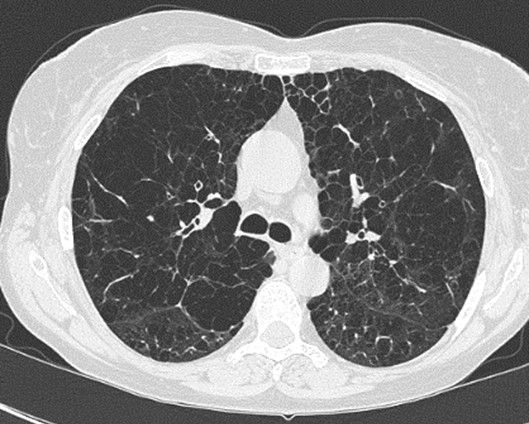

· CT scan ngực: Chụp CT scan độ phân giải cao có hình ảnh khí phế thủng khu trú hoặc lan tỏa 2 phế trường, đặc trưng bởi những vùng phổi sáng hơn nhu mô phổi bình thường. Kết hợp với phần mềm đo được chỉ số khí phế thủng (Emphysema Index) giúp định lượng được mức độ khí phế thủng trên phim CT scan.

Hình 3: Hình ảnh khí phế thủng trên phim CT scan ngực.